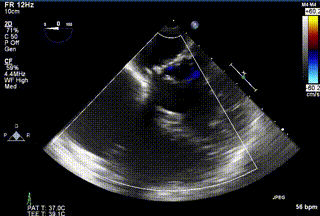

2021年12月24日,復(fù)旦大學(xué)附屬中山醫(yī)院葛均波院士團(tuán)隊(duì)成功應(yīng)用LuX-Valve Plus為一例極重度三尖瓣反流(TR)合并房顫、房缺的患者完成了經(jīng)血管三尖瓣置換術(shù),這是在前基礎(chǔ)上,本周完成的第三例經(jīng)血管三尖瓣置換手術(shù),葛均波院士、周達(dá)新教授等與心外科魏來教授、賴顥教授,心超室的潘翠珍教授、李偉教授及麻醉科的郭克芳教授共同完成了本周手術(shù),均獲得圓滿成功!患者術(shù)后超聲顯示無TR,臨床癥狀明顯改善。本周手術(shù)的成功也為LuX-Valve Plus救治性臨床研究添上了濃墨重彩的一筆。

三例患者入院后,葛均波院士團(tuán)隊(duì)周達(dá)新教授、潘文志教授、張?jiān)床┦俊㈥惿┦考靶某业呐舜湔浣淌?、李偉教?/strong>對(duì)患者的情況進(jìn)行詳細(xì)評(píng)估和討論,最終決定為三例患者選擇LuX-Valve Plus40mm、50mm和50mm型號(hào)的瓣膜進(jìn)行手術(shù)治療。手術(shù)后即刻拔除氣管插管,術(shù)后患者三尖瓣反流癥狀得到顯著改善,復(fù)查心超結(jié)果顯示人工三尖瓣瓣膜支架固定穩(wěn)定,瓣葉關(guān)閉形態(tài)未見異常,未見明顯反流。